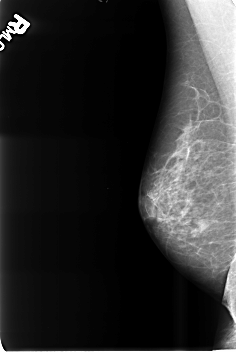

B_3471_1.RIGHT_CC

RIGHT_CC LINES 4600 PIXELS_PER_LINE 3064 BITS_PER_PIXEL 12 RESOLUTION 50 NON_OVERLAY